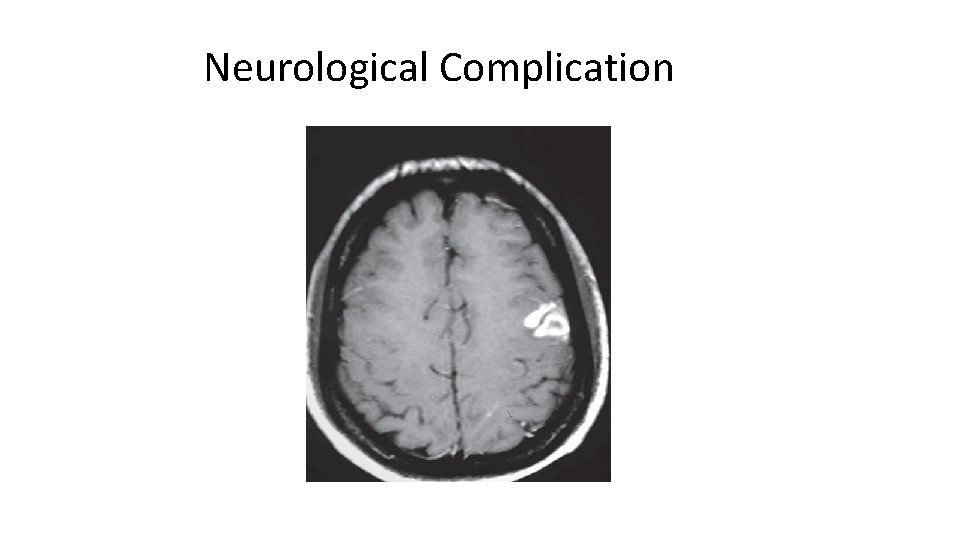

Complications-1 • Congestive Cardiac Failure (Commonest complication) • • Valve Destruction Myocarditis Coronary artery embolism and MI Myocardial Abscesses • Neurological Manifestations (1/3 cases) • Major embolism to MCA territory ~25% • Mycotic Aneurysms 2 - 10%

Neurological Complication